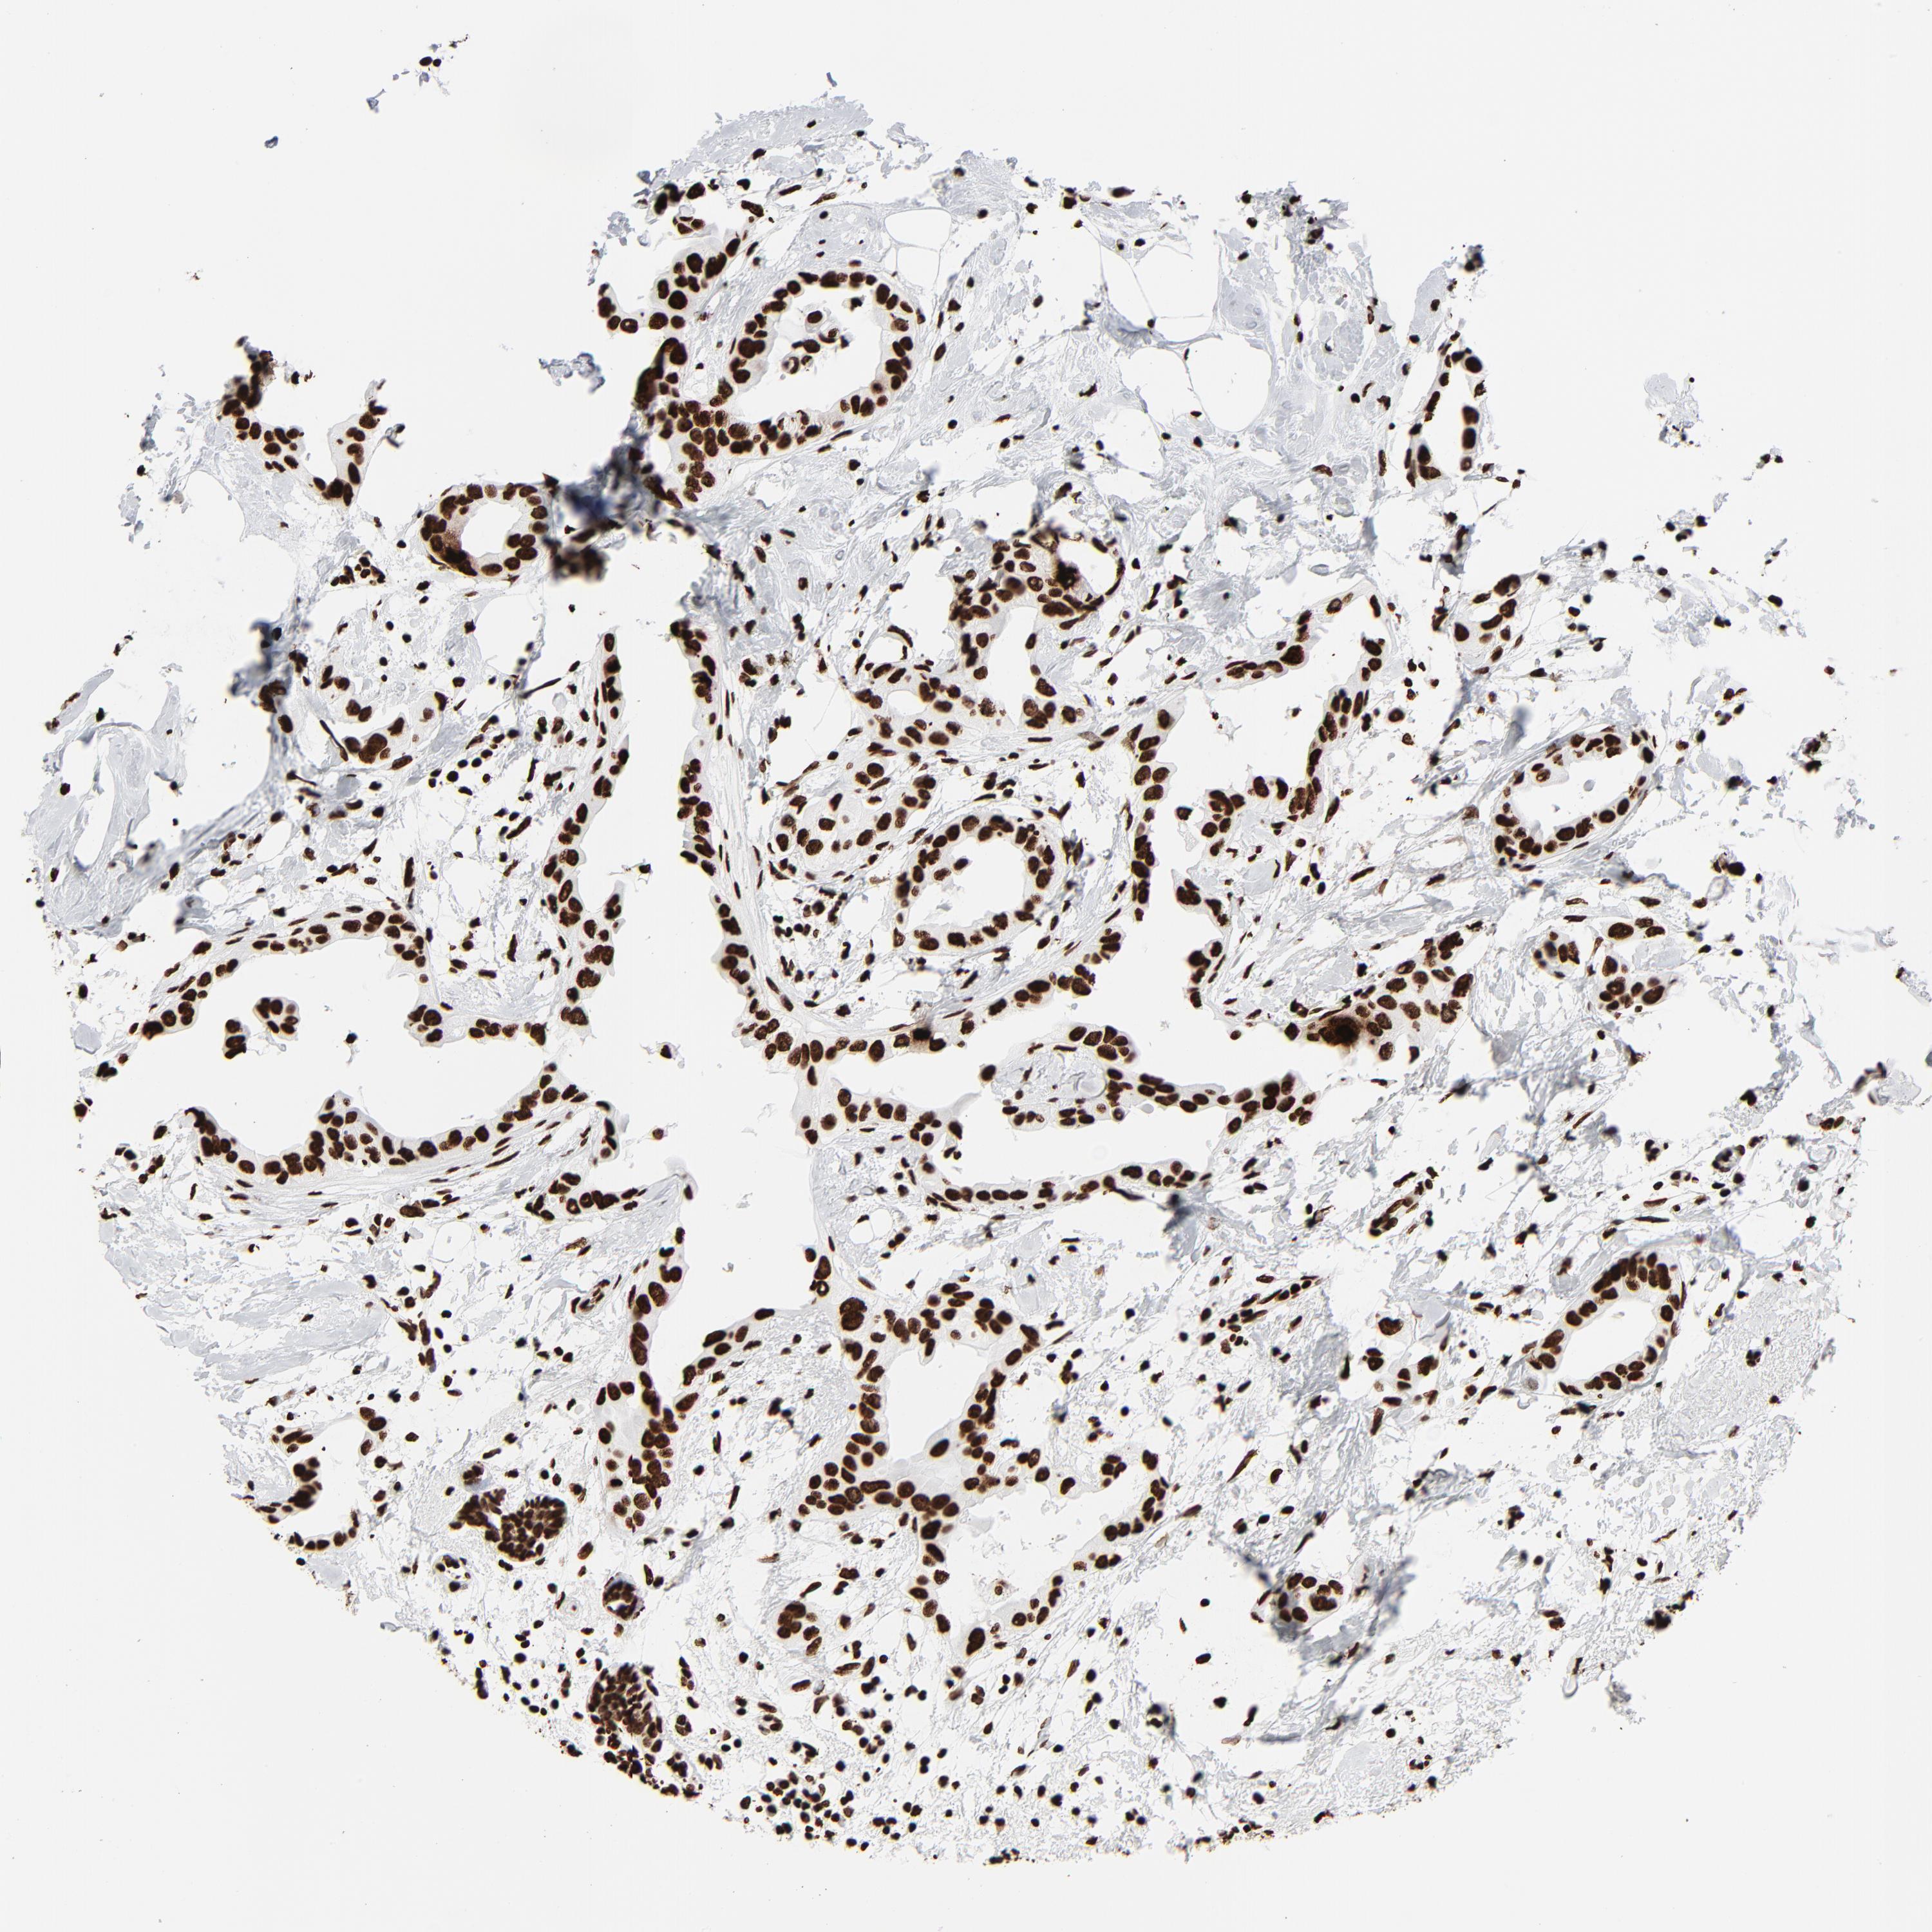

CANCER BREAST CANCER Show tissue menu

BRCA TCGA BRCA VALIDATION PROTEIN EXPRESSION